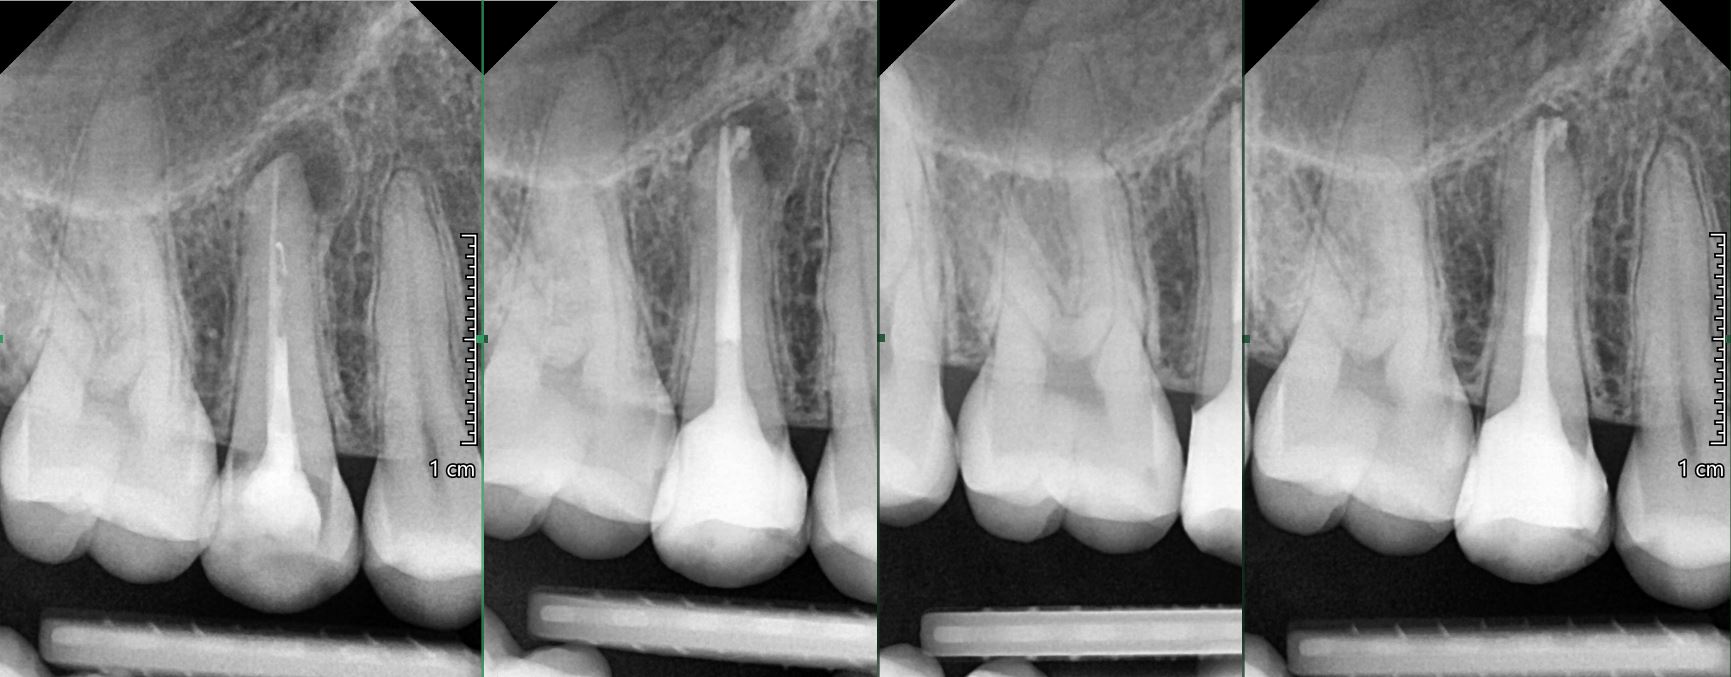

OŠETŘENÍ PACIENTŮ POD OPERAČNÍM MIKROSKOPEM

Nabízíme možnost delegovat Vaše pacienty k (re)endodontickému ošetření pod operačním mikroskopem.